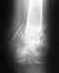

Ось (по одной проекции) выглядит приемлемо. Похоже, есть значительный дефект. Мы бы заменили аппарат на гвоздь с антибактериальным покрытием. Что предложат в ЦИТО - не знаю. И в Москве много куда еще можно обратиться, можно даже к нам приехать.